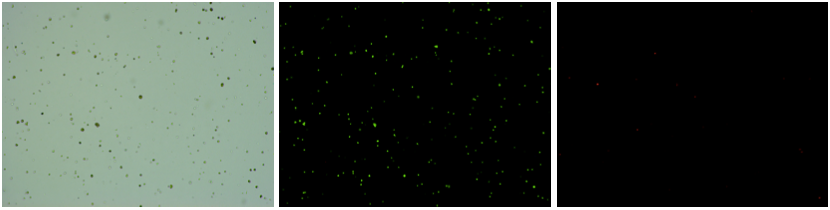

人腎組織樣品,細胞活率:97.86%,結(jié)團率:8.68%

Tips:腎臟組織中細胞種類繁多且復(fù)雜,部分細胞類型解離過程中容易死亡,腎足細胞等粒徑比較大,建議采用單細胞核的方式,獲得的細胞類型更加全面。